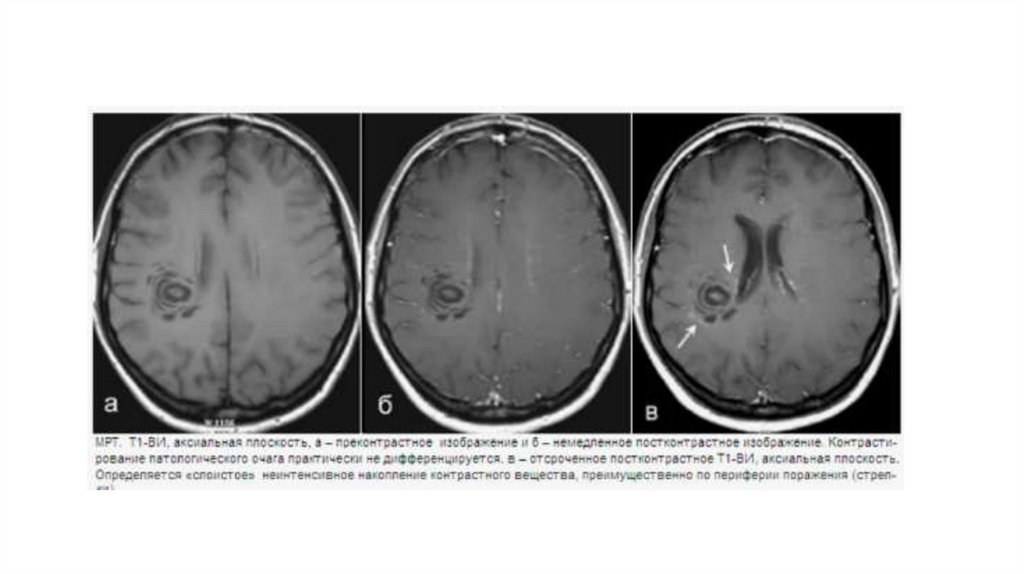

Концентрический склероз Бало – редкое демиелинизирующее заболевание с

монофазным прогрессирующим течением, характеризующееся появлением в качестве

патоморфологического субстрата концентрических колец демиелинизации,

чередующихся со слоями ремиелинизации. Поэтому типичным является визуализация

с помощью МРТ концентрических кругов, напоминающих завитки, «спил дерева»,

«чешуи лука» на Т2-ВИ и постконтрастных изображениях. Очаги расположены в

гемисферах мозга, асимметричны, иногда выявляются и в стволе мозга, и в мозжечке.

Чаще концентрический склероз Бало рассматривают как один из вариантов

рассеянного склероза. Описаны формы, при которых наряду с характерными

концентрическими очагами присутствовали типичные для рассеянного склероза

очаги. Бало-подобные очаги описаны и у пациентов с типичным течением

рассеянного склероза.